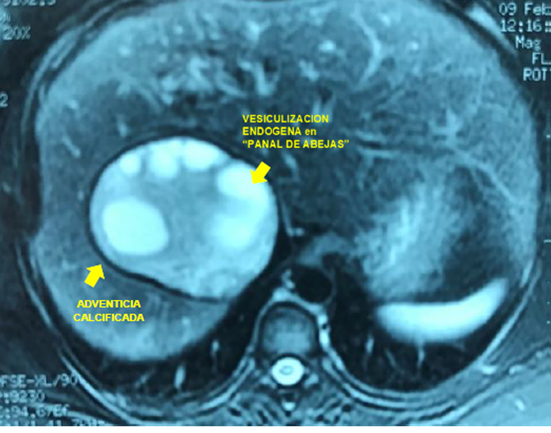

Esta comunicación muestra la correlación imagenológico-quirúrgica (Figura 1) de los estudios habituales para el diagnostico de quiste hidático en su forma crónica más frecuente: conteniendo "vesículas hijas" producto de la vesiculización endógena - responsable del signo patognomónico del “panal de abejas “ (Figura 2) - que es un indicador de vitalidad y complicación del quiste. La adventicia -muy gruesa y calcificada- se observa como una lámina blanca bien definida en la TC, (Figura 3) bajo forma de una lamina hipointensa en la RNM (Figura 4) e hiperecogénica en la ecografía (Figura 2) y corresponde a la reacción inflamatoria crónica del parénquima hepático por estimulo inmunológico de la lámina periquística hidática ,que en la evolución se infiltra de calcio .Las calcificaciones se visualizan mejor mediante TC. (Figura 3).La colangio-RNM es específica para establecer las relaciones quiste con el sistema biliar. (Figura 5)

Figura 4: La ​​resonancia nuclear magnética (RNM) aporta imágenes de mayor precisión y está indicada para quistes con complicaciones biliares.